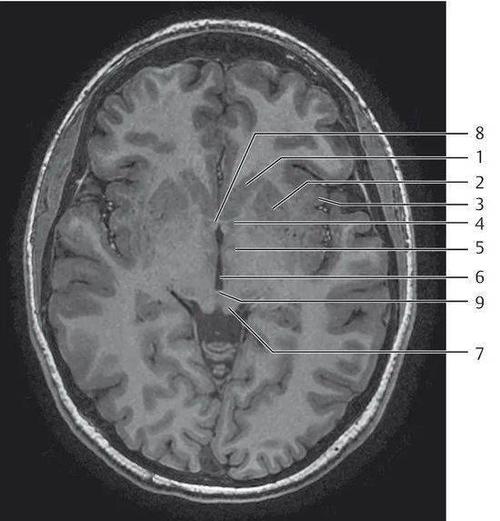

超详细颅脑mri常用解剖

334.头部磁共振解剖